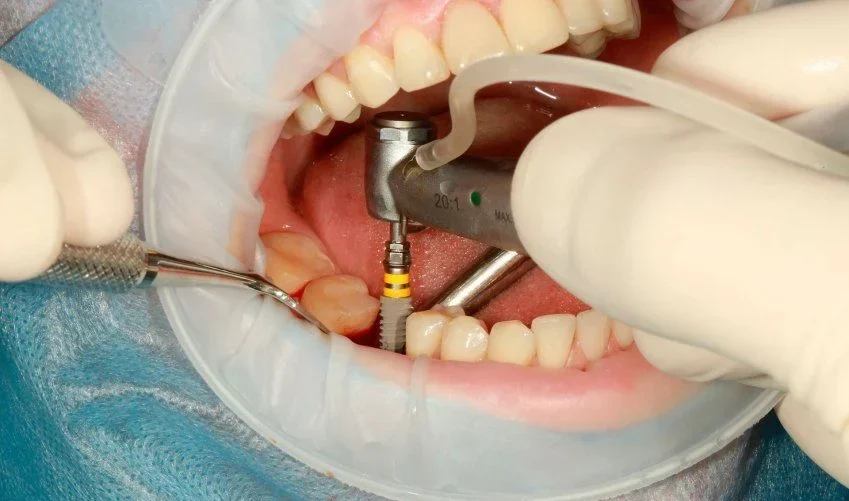

El implante se inserta en el hueso maxilar o mandibular mediante un procedimiento seguro y mínimamente invasivo. Dependiendo del caso, se puede aplicar carga inmediata o esperar el tiempo de osteointegración, asegurando que el implante quede estable y rodeado de hueso sano.

El implante se inserta en el hueso maxilar o mandibular mediante un procedimiento seguro y mínimamente invasivo. Dependiendo del caso, se puede aplicar carga inmediata o esperar el tiempo de osteointegración, asegurando que el implante quede estable y rodeado de hueso sano.